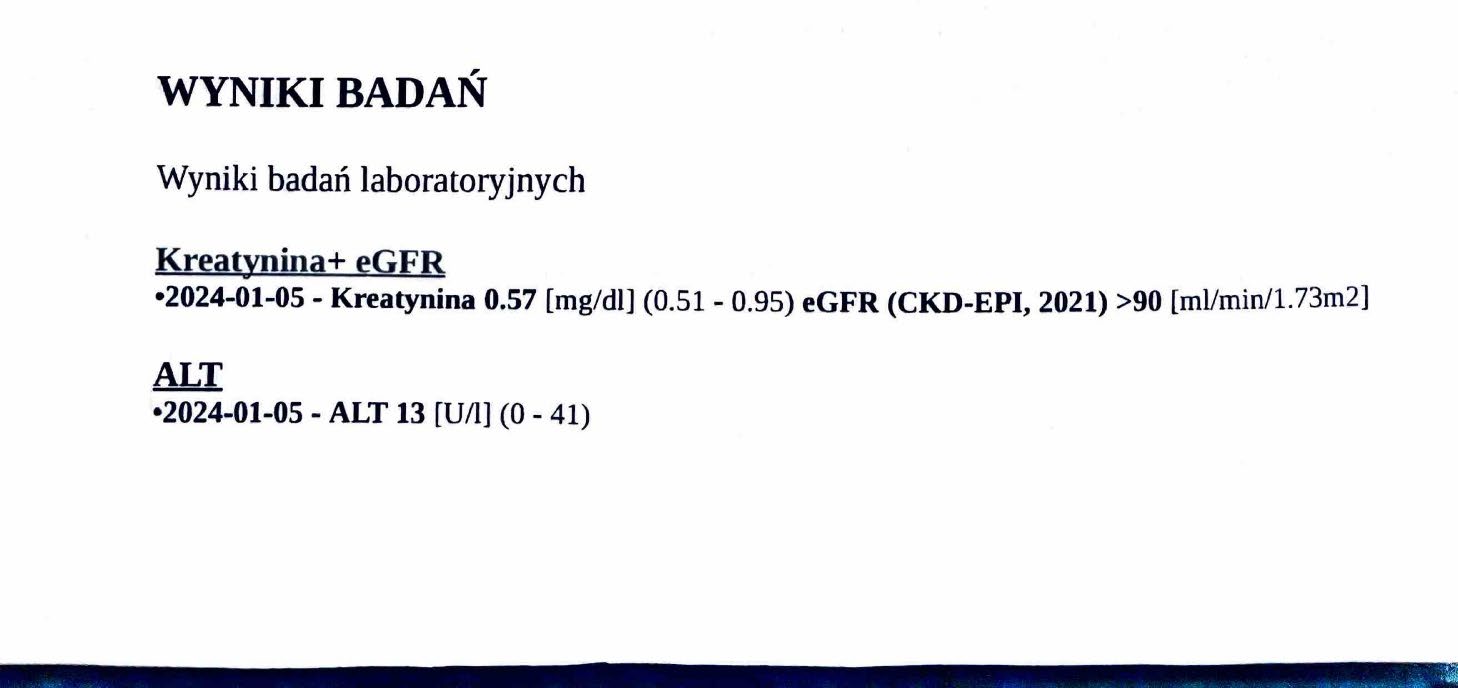

EFEKT PREPARATU NA RAKA PIERSI

Kobieta lat 71, rak piersi w IV stadium, zaawansowane stadium metastazy. W trakcie stosowania preparatu odnotowano spadek markerów Ca 15-3 z wartości 140,0 U/ml do 78,3 U/ml oraz spadek markeru CEA z 11,8 ng/ml do 8,4 ng/ml w zaledwie 3 miesiące, odnotowano stabilność szpiku. Wyniki wykazują zahamowanie progresji, dodatkowo odnotowano cechy uzupełniające terapię farmakologiczną, więc jest to jeden z przykładów wspomagania leczenia systemowego.